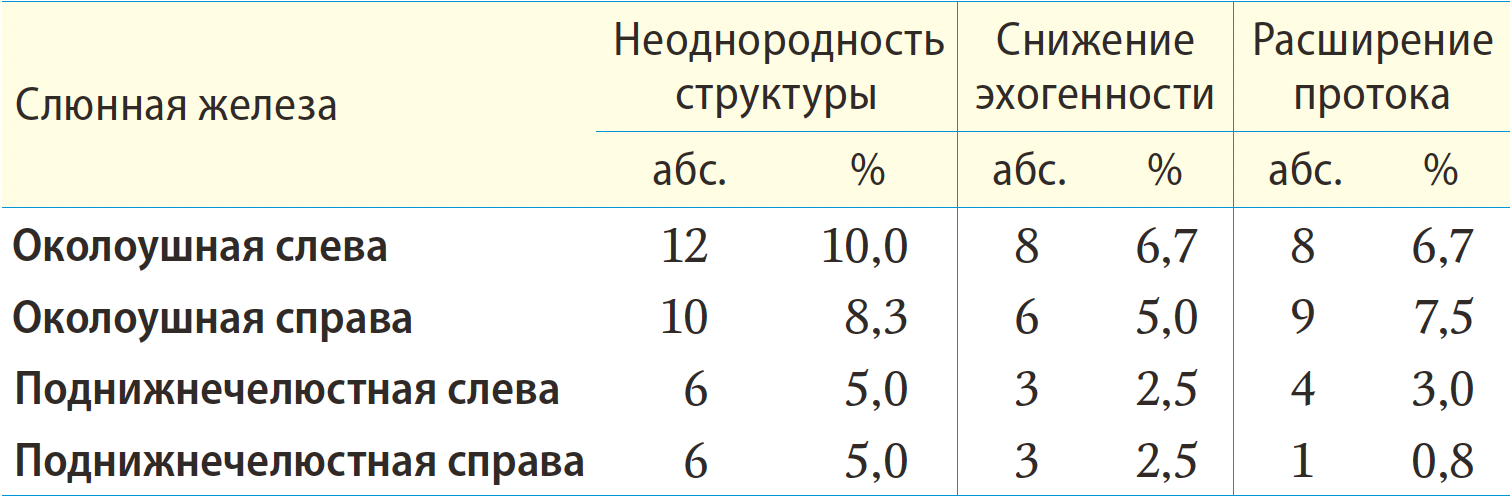

Результаты. Было выделено 3 эхографических признака состояния слюнных желез при сиаладените после радиойодтерапии: изменение эхогенности, расширение протоковой системы слюнных желез, неоднородность структуры. Изменение эхогенности наиболее часто происходит в левой околоушной слюнной железе (ОСЖ) — 6,7%. У пациентов с поражением ОСЖ справа и слева показатель расширения протока составлял 7,5 и 6,7% соответственно (расширение до 3 мм). Неоднородность структуры слюнных желез наиболее часто проявлялась в левой ОСЖ — 10%.

При сиаладените на фоне РЙТ происходят такие изменения паренхимы и протоковой системы слюнных паттернах картины УЗИ: появление неоднородности структуры железы, снижение эхогенности и расширение протоковой системы (табл. 1, 2).

Расширение протока слюнной железы

У пациентов с поражением ОСЖ справа проявилось в 7,5% случаев, слева — у 6,7% пациентов, медиана расширения протока составила 2 мм [1,8—2,2 мм] при максимальном расширении до 3 мм (рис. 1).

В контрольной группе этот показатель составляет в левой и правой ПСЖ по 4,2 и 5% соответственно, медиана расширения протока составила 0,5 мм [0,3—0,6] при максимальном расширении до 0,8 мм (рис. 2).

При сравнении степени расширения протоковой системы было отмечено более значительное расширение протоковой системы у пациентов после РЙТ в основной группе (p=0,003).

Неоднородность структуры

Неоднородность структуры является наиболее частым УЗ-паттерном, который можно обнаружить при УЗИ больших слюнных желез (p<0,001). У пациентов после радионуклидной терапии такие изменения чаще всего имеются в левой ОСЖ — 10%, в правой ОСЖ — 8%, в ПСЖ — 5%. В контрольной группе людей этот показатель не превышает 2% в области каждой ПСЖ. При сравнении частоты регистрации неоднородности структуры было выявлено значимо более частое наличие неоднородности в структуре ОСЖ после РЙТ (p<0,001), а в ПСЖ значимых различий не получено (p=0,151).